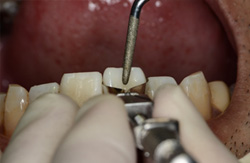

![]() |

神経の露出した処置を行います。上の部分を少しだけ取って残りの部分を残します。部分的な断髄といいます。根の治療(歯内療法)をするときは必ずラバーダム防湿(緑の膜)をおこないます。感染防止のためラバーダムをしない根の治療はありえません。一番の成功のポイントです。 |